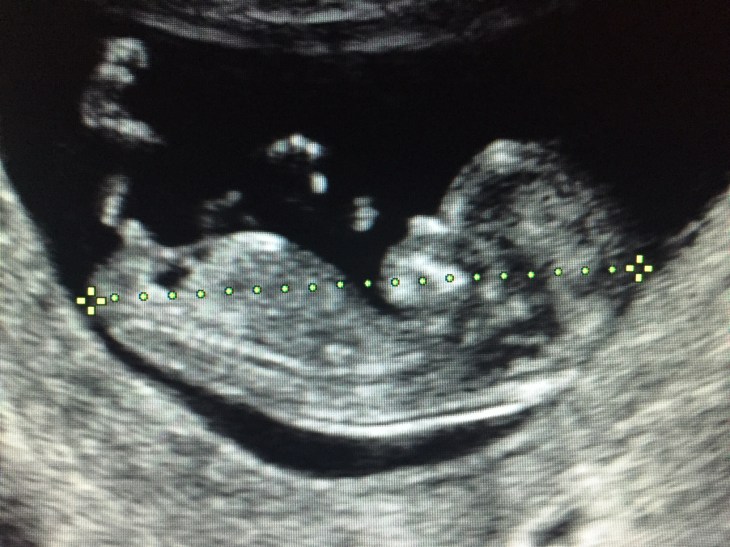

Antes de la 6ta semana, contadas a partir de la fecha de ultima regla, el eco no aporta mucha información y al contrario, puede generar stress/ansiedad, mientras que el eco realizado entre la 6ta y la 10ma semana, además de regalarte la emoción de ver/oír el corazón de tu bebé latiendo, se va a convertir en la cédula de identidad de tu bebé o mejor dicho, su partida de nacimiento intrauterina.

Si, así mismo, es que ese primer eco es la mejor herramienta de la que disponemos para datar (calcular el tiempo) de tu embarazo de la manera más exacta posible, en quienes no recuerdan con exactitud la fecha de ultima menstruación o tienen ciclos menstruales irregulares. http://www.natalben.com/guia-embarazo/embarazo-primer-mes/edad-gestacional

Resulta que todos los embriones, durante las primeras semanas, tienen la misma velocidad de crecimiento y es solo después del segundo trimestre de embarazo cuando los fetos adquieren lo que conocemos como variabilidad biológica, es decir, que cada uno adquiere una velocidad de crecimiento que va a depender de la genética (el tamaño de los padres y hermanos), de las patologías que acompañen el embarazo como hipertensión arterial que a menudo se asocia con bebés pequeños o diabetes gestacional que por el contrario se asocia con bebés grandes.

La moraleja de este artículo es que guardes el primer eco y que la edad de embarazo que de él derive no se modifique más adelante por cambios en el peso/medidas del bebé.